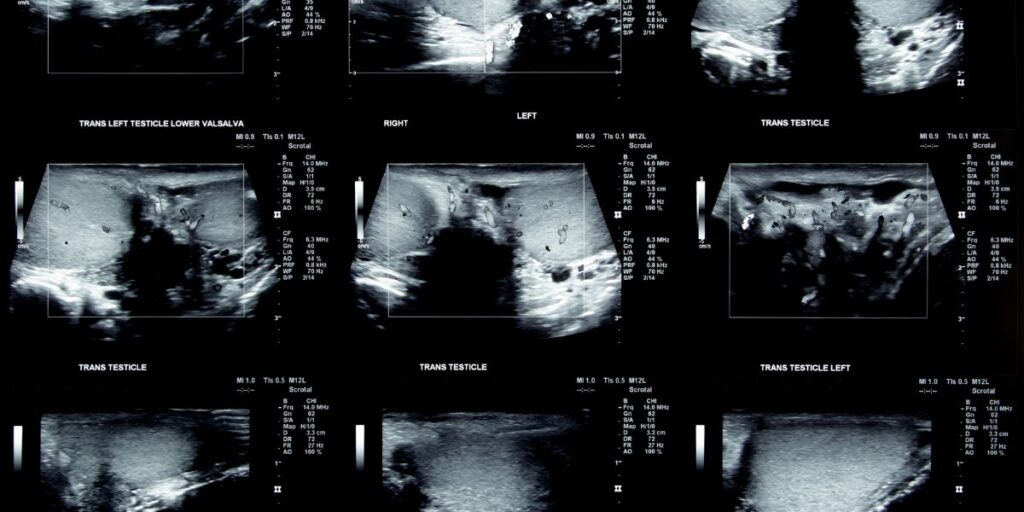

L’Ecografia Testicolare sfrutta onde sonore ad alta frequenza per creare immagini dettagliate dei testicoli e delle strutture circostanti. Questo esame, indolore e sicuro, è essenziale per individuare anomalie come noduli, cisti o altre patologie che potrebbero compromettere la funzionalità del sistema riproduttivo maschile.

Il medico applica un gel trasparente sulla pelle dello scroto, che serve a migliorare la trasmissione delle onde sonore. Successivamente, utilizza una sonda ecografica per generare immagini in tempo reale dei testicoli. Le onde sonore emesse dalla sonda vengono riflesse dai tessuti, creando un’immagine che permette di identificare eventuali anomalie strutturali o funzionali.